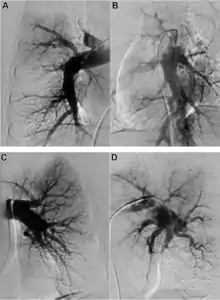

Example of a side-selective pulmonary artery angiogram (A and B right pulmonary artery, C and D left pulmonary artery) in digital subtraction technique of a patient with CTEPH. Panels A and C represent anterior-posterior projections, panels B and D represent lateral projections.

Early diagnosis still remains a challenge in CTEPH, with a median time of 14 months between symptom onset and diagnosis in expert centres.[7] A suspicion of PH is often raised by echocardiography, but an invasive right heart catheterisation is required to confirm it.[6] Once PH is diagnosed, the presence of thromboembolic disease requires imaging. The recommended diagnostic algorithm stresses the importance of initial investigation using an echocardiogram and V/Q scan and confirmation with right heart catheter and pulmonary angiography (PA).[8]

Both V/Q scanning and modern multidetector CT angiography (CTPA) may be accurate methods for the detection of CTEPH, with excellent diagnostic efficacy in expert hands (sensitivity, specificity, and accuracy of 100%, 93.7%, and 96.5% for V/Q and 96.1%, 95.2%, and 95.6% for CTPA).[9] CTPA alone cannot exclude the disease, but may help identify pulmonary artery distension resulting in left main coronary artery compression, pulmonary parenchymal lesions (e.g. as complications from previous pulmonary infarctions), and bleeding from bronchial collateral arteries.[10] Today, the gold standard imaging remains invasive pulmonary angiography (PAG) using native angiograms or a digital subtraction technique.